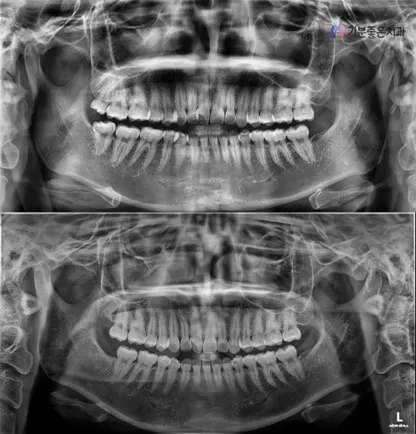

01 - Panoramic X-ray and Diagnosis

The position and shape of the wisdom tooth are confirmed through panoramic imaging and an oral examination. If necessary, CT imaging is used to also reference the surrounding teeth and anatomical structures.